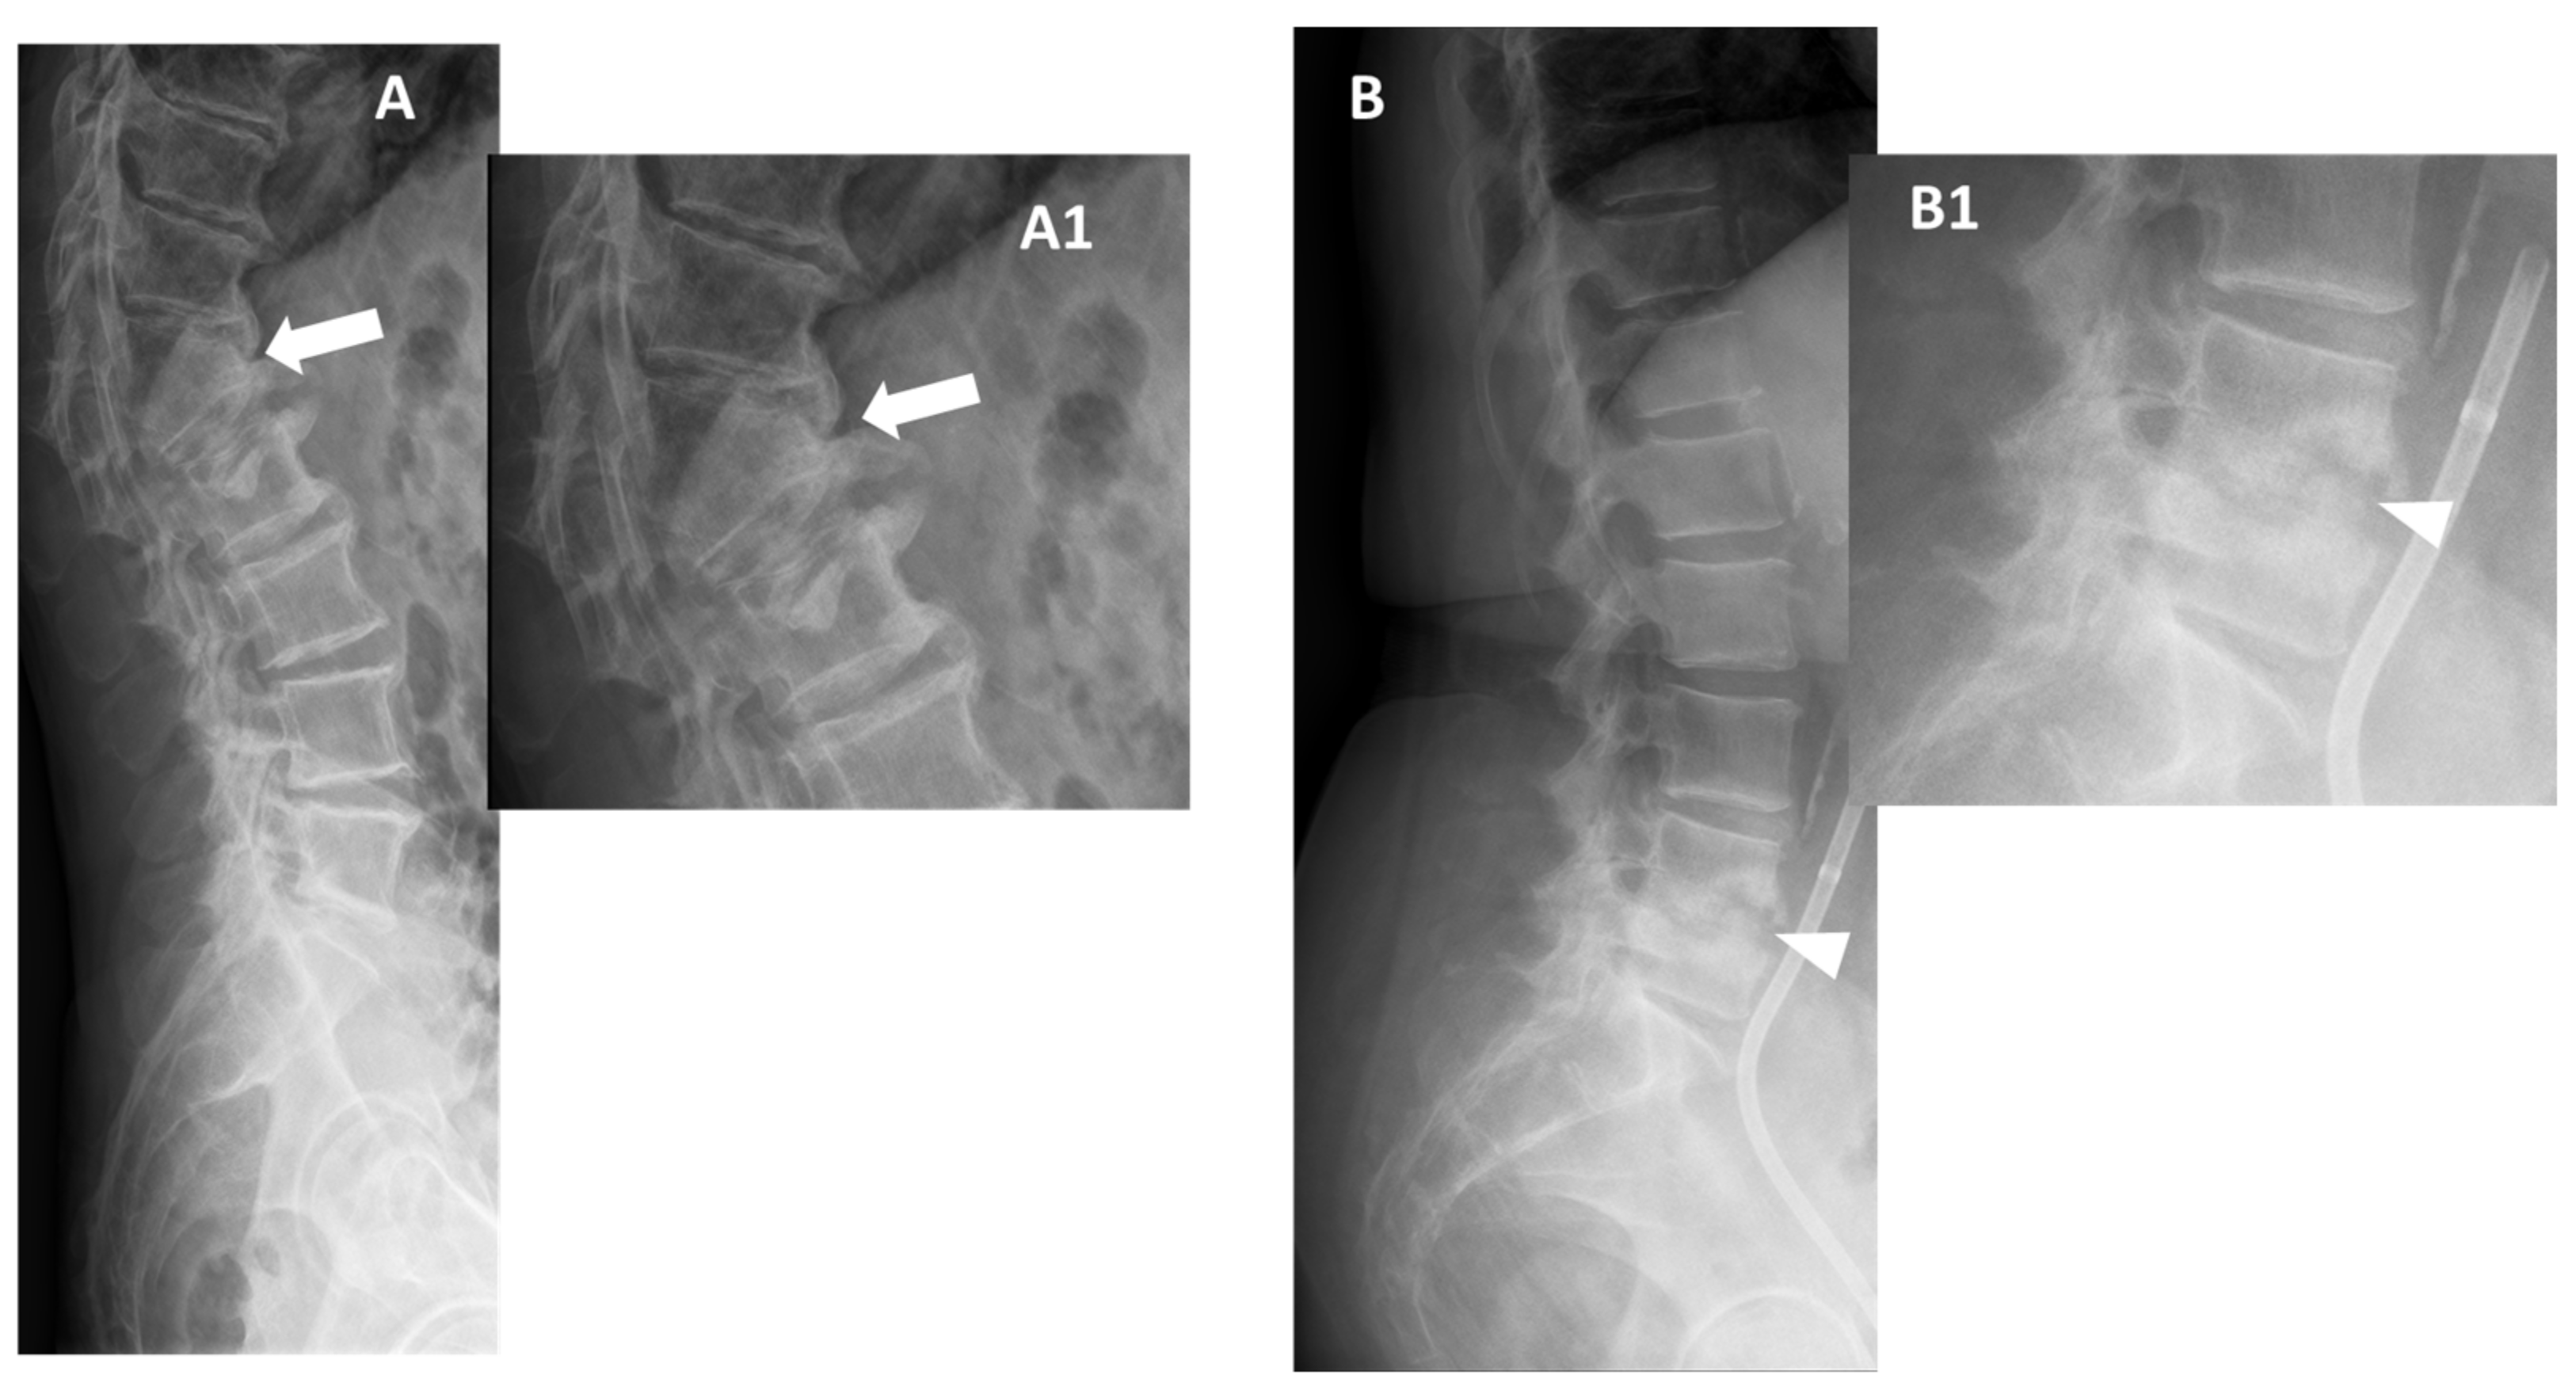

Figure 2. Conventional radiographs, lateral views (Panel A, and Magnification A1), of a 77-year-old male with previous pyogenic spondylodiscitis of T12-L1 vertebral bodies (partially collapsed and fused—arrows). Conventional radiographs, and lateral views (Panel B and Magnification B1) of a 64-year-old female with spondylodiscitis of L4–L5 vertebral bodies (thick endplate erosions are detected—arrowheads).